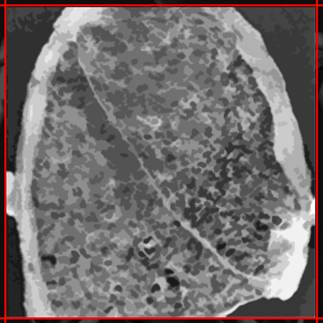

7-8 La doctora sitúa en la pantalla de luz la radiografía de los pulmones y la mira con una lupa. El trabajador observa atentamente desde detrás.

Voz en off Chica- El estudio radiológico del tórax. En función de los resultados se podrán hacer otras pruebas como una tomografía computada o una tomografía computada de alta resolución.